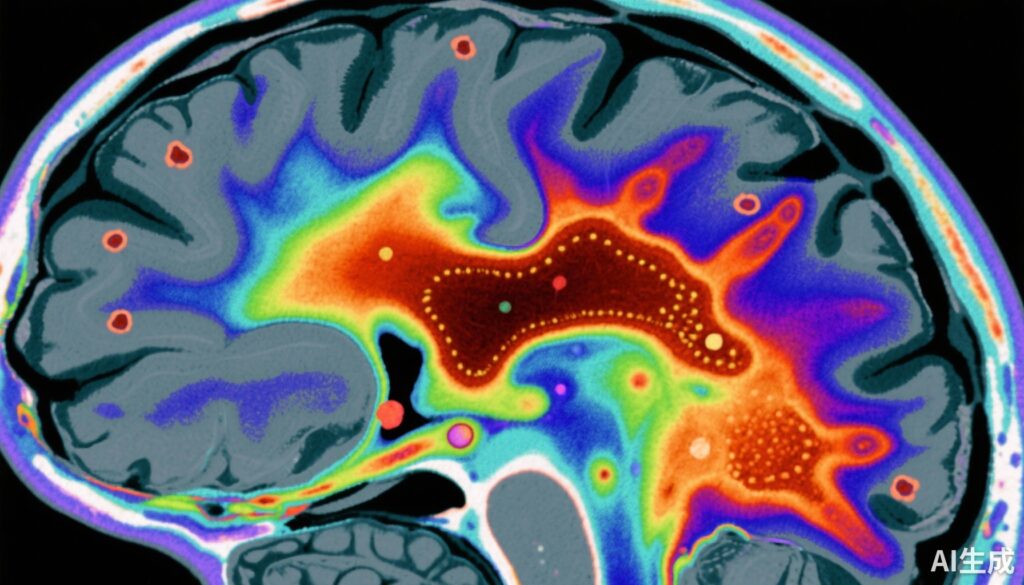

Nghiên cứu đối chứng này do Vano et al. thực hiện bao gồm 159 người tham gia: 79 bệnh nhân tâm phân liệt giai đoạn đầu (bao gồm cả những người chưa dùng hoặc đã ngừng dùng thuốc chống loạn thần) và 80 người khỏe mạnh. MRI định lượng từ hóa (QSM) được sử dụng để định lượng mức độ từ hóa – một đại diện cho sắt não – ở substantia nigra và ventral tegmental area (SN-VTA).

Nghiên cứu tìm thấy giảm đáng kể về mặt thống kê trong mức độ từ hóa ở vùng SN-VTA ở bệnh nhân tâm phân liệt so với nhóm đối chứng, với kích thước hiệu ứng (Cohen’s d) là -0.66 (95% CI, -0.98 đến -0.34). Điều này cho thấy nồng độ sắt não thấp hơn ở vùng dopaminergic midbrain quan trọng này.

Phân tích tương quan cho thấy mối quan hệ nghịch đảo đáng kể (r = -0.44) giữa mức độ từ hóa SN-VTA và khả năng tổng hợp dopamine ở striatum (Ki cer) được đo bằng PET. Vì vậy, cá nhân có nồng độ sắt não thấp hơn có tổng hợp dopamine cao hơn ở striatum, hỗ trợ giả thuyết rằng sự thiếu hụt sắt não có thể thúc đẩy hyperdopaminergia.

Phân tích khu vực cho thấy vùng ventral SN-VTA có mối liên hệ mạnh mẽ nhất, làm nổi bật tầm quan trọng đặc biệt của tiểu khu vực này đối với rối loạn dopamine trong bệnh tâm phân liệt.